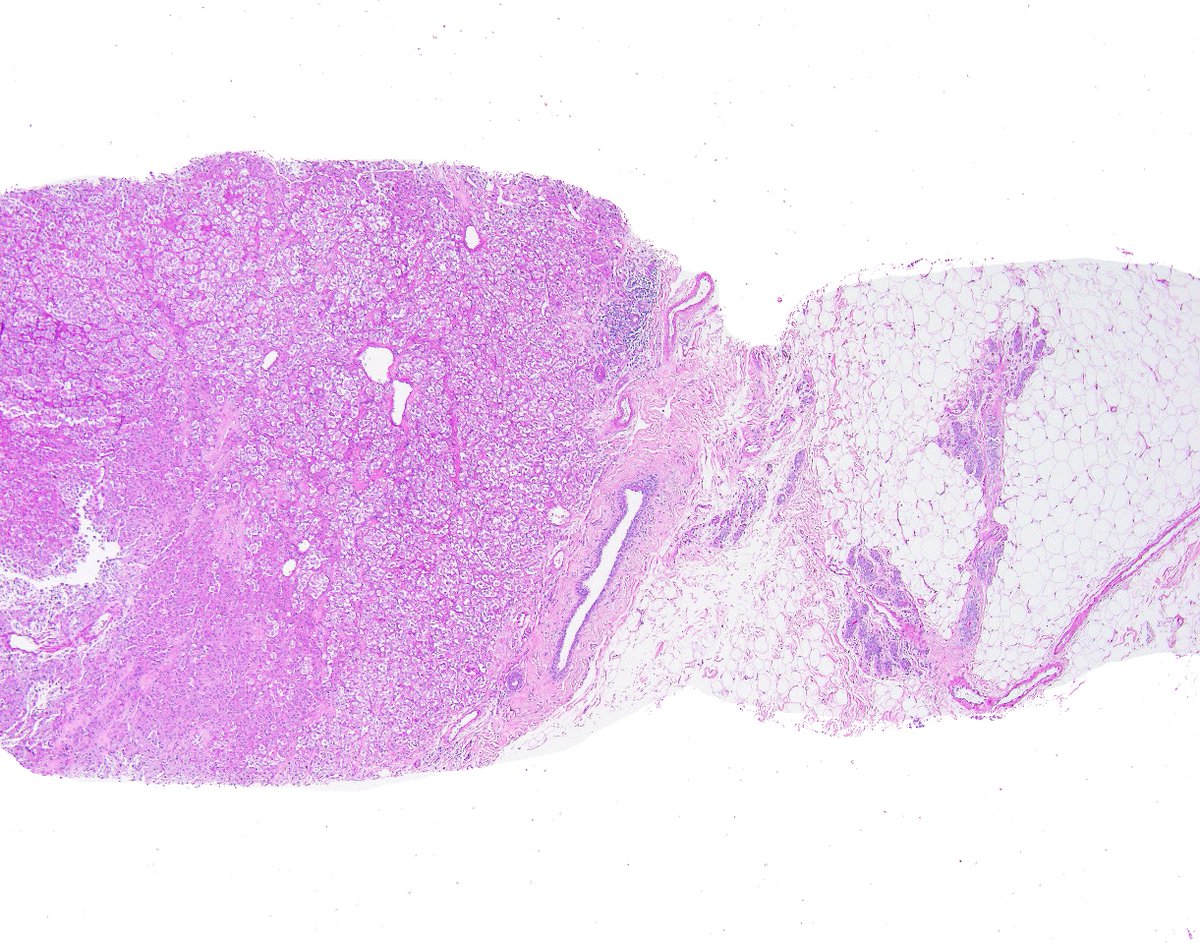

Does This Imaging Make Me Look NFATC2? The Value of... : The American Journal of Surgical Pathology journals.lww.com/ajsp/abstract/…

Does this imaging make me look NFATC2?